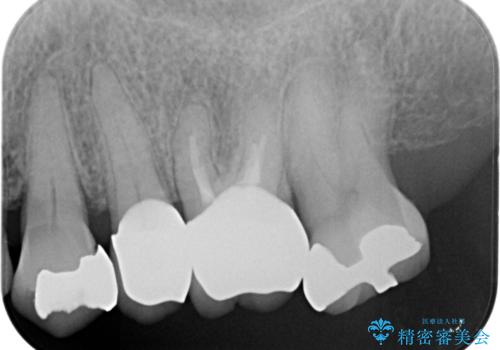

- 左下の大臼歯(6番)の根の治療を行いました。

その代わり、現在ある歯をしっかり治療することになり、左上下の治療を行っています。

左下6番の根管治療は六本木院の林院長にお願いしています。

左上56間が狭かったため、写真にはないですが、セパレーションを2回ほど行い、歯根間距離を広げてから処置を行っています。

そのまま無理やり歯型を取って製作するよりも、ご自身で清掃ができる形態にできるため、長期的な予後が期待できます。